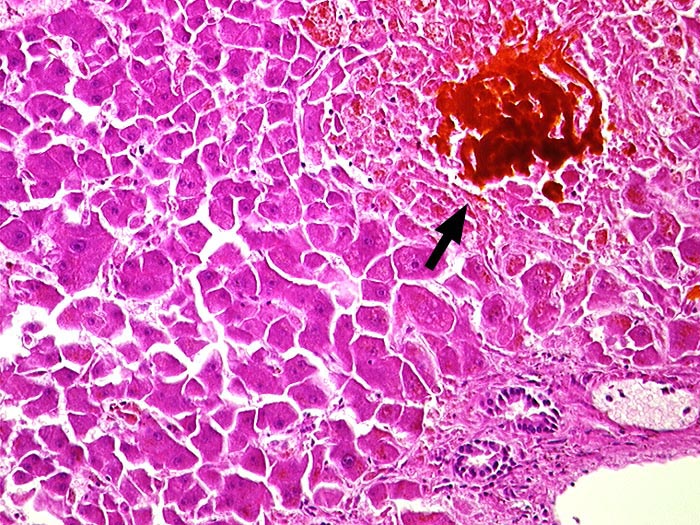

PathoPic ID 886 - Galleinfarkt bei extrahepatischem Verschlussikterus

Galleinfarkt bei extrahepatischem Verschlussikterus

Gallig durchtränkte

►

Gruppennekrose. Rechts unten ist ein Portalfeld angeschnitten.

Choledocholithiasis.